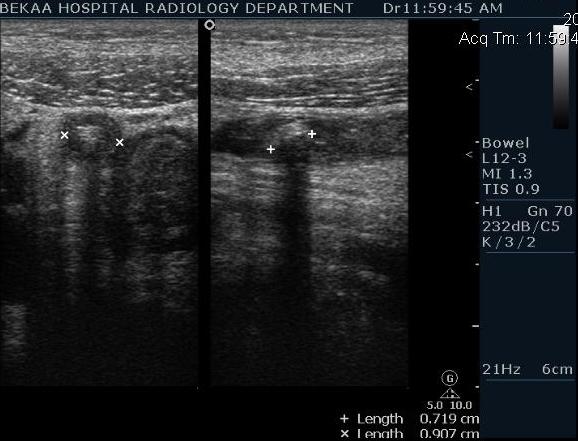

после начинаем производить хорошую компрессию датчиком попрося пациента сообщить в какой точке боль наиболее выражена; медленными движениями датчика сканируем область наибольших болевых ощущений и как правило находим утолщенный отросток. Лучше начинать с поперечной визуализации и идти к верхушке аппендикса что бы убедится что это аппендикс и он заканчивается, а не тонкая кишка (которая если и закончится то только переходя в слепую); потом надо аккуратно развернуть продольно датчик и посмотреть от верхушки аппендикса к слепой. Норма диаметра: 3-4 мм; 5-6 мм под вопросом (клиника решает; но я в катаральный аппендицит не верю); 7-8 мм и больше, не компремируемый (фиксированный отросток)-острый аппендицит! Помимо наличие утолщенного аппендикса; признака "бычьего глаза" (bull-eye sign) при поперечном сканировании; надо обращать внимание на присуствие аппендоколитов в просвете; деструкцию стенки и свободной жидкости в зоне интереса.